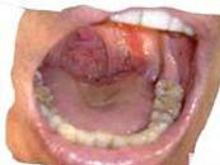

咽部黏膜水腫蒼白咽壁扁桃體及軟齶,有瘀血點或瘀斑繼發感染侵及黏膜黏膜下層及深達肌層出現壞死及潰瘍上面復蓋灰白色假膜嚴重者組織壞死處,呈棕褐色並有出血傾向扁桃體及舌根部淋巴組織無炎症性腫大,在急性白血病早期,常有全身各部位無痛性淋巴結腫大咽部潰爛,可引起劇烈疼痛吞咽困難口臭及有時發生張口受限等症狀。